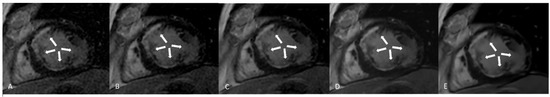

LGE sequences acquired using an artificial intelligence reconstruction deep learning algorithm. Forty-one-year old patient with previous myocardial infarction on anterior, anteroseptal, inferoseptal, inferior, and inferolateral segments (arrows, (A–E), respectively). Image noise decreased progressively with increase in AIRDL reconstruction in both 2D-SSLGE ((A): 2D-SSLGE AIRDL 0%, (B): 2D-SSLGE AIRDL 25%, (C): 2D-SSLGE AIRDL 50%, (D): 2D-SSLGE AIRDL 75%, (E): 2D-SSLGE AIRDL 100%). 2D-SSLGE—2D single segmented inversion recovery gradient echo late gadolinium enhancement sequences; AIRDL—artificial intelligence reconstruction deep learning.